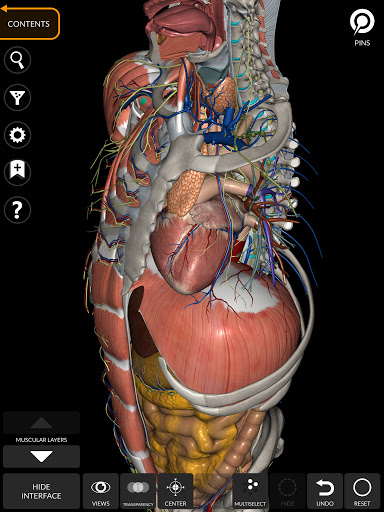

يتيح لك "Anatomy 3D Atlas" دراسة التشريح البشري بطريقة سهلة وتفاعلية.

من خلال واجهة بسيطة وبديهية، من الممكن ملاحظة كل بنية تشريحية من أي زاوية.

تتميز النماذج التشريحية ثلاثية الأبعاد بتفاصيل خاصة ودقة تصل إلى 4K.

يسهل التقسيم حسب المناطق والمناظر المحددة مسبقًا مراقبة ودراسة الأجزاء الفردية أو مجموعات الأنظمة والعلاقات بين الأعضاء المختلفة.

• الجهاز العضلي الهيكلي

• الجهاز القلبي الوعائي

• تصور العضلات من خلال مستويات الطبقات من الطبقات السطحية إلى الأعمق